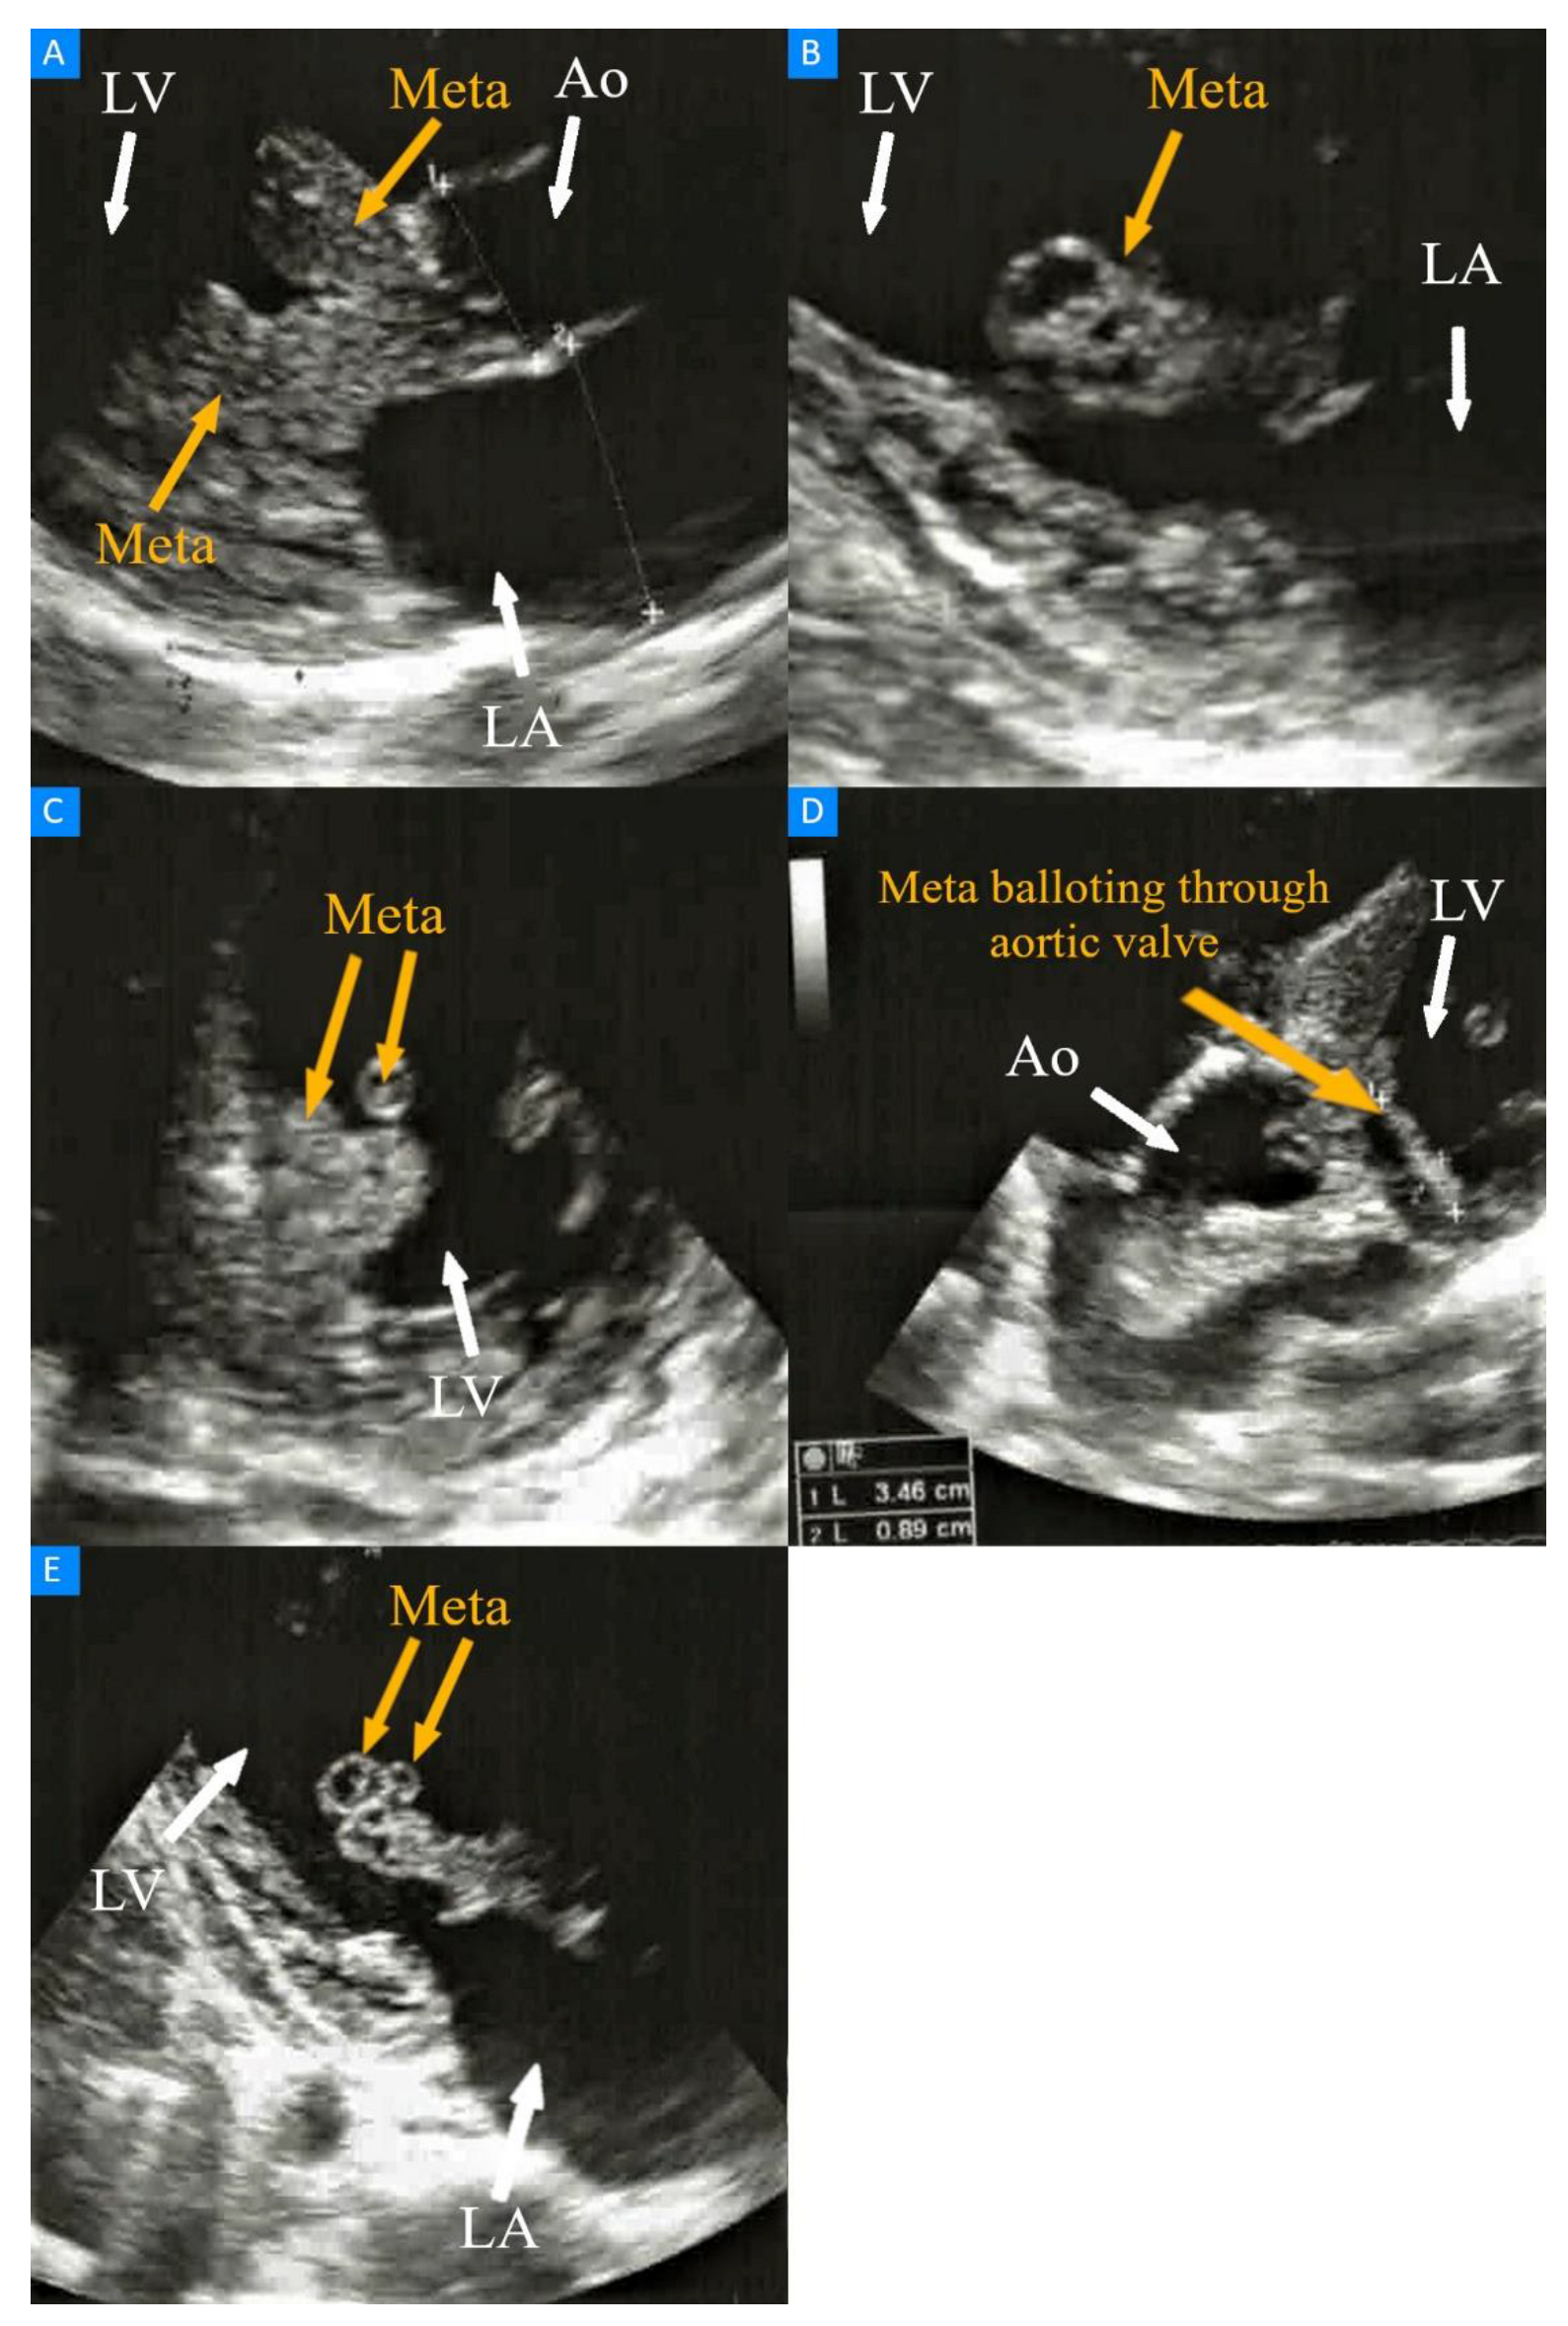

Heart Metastases of Clear Cell Renal Cell Carcinoma